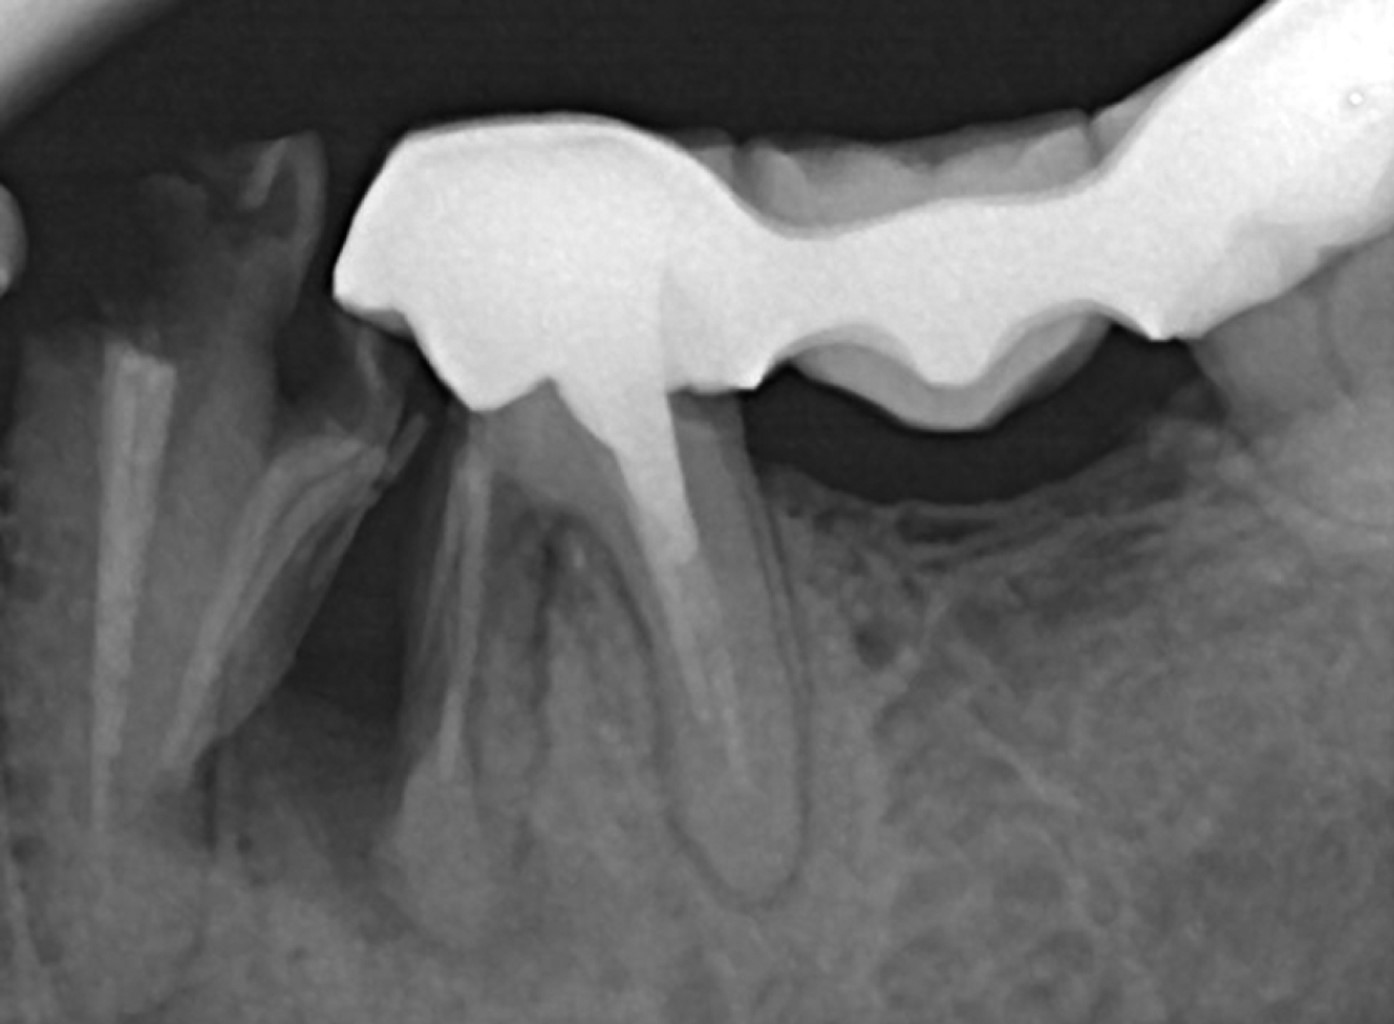

• 5. Fractura radicular vertical: involucra sólo a la raíz. La corona dentaria impide observar desde la boca la lesión, es de diagnóstico muy complejo, ya que a veces sólo presenta síntomas periapicales sin que la lesión se observe radiográficamente hasta que se produce el estallido radicular. La causa más frecuente de fractura radicular vertical es el poste inadecuado en forma o tamaño, la remoción excesiva de tejido dentinario radicular y a veces la tendencia en algunos molares por su forma anatómica, sobre todo en raíces anchas en sentido vestíbulo lingual. El tratamiento va desde la extracción del diente hasta el retiro de la raíz comprometida. La prevención contempla el uso de postes de fibra de vidrio, ser conservador con la remoción de dentina radicular o reducir las fuerzas de condensación durante la obturación (Figura 5).

Se seleccionaron únicamente aquellos casos en los que se pudo obtener evidencia clínica, fotográfica y radiográfica de la presencia de por lo menos una fisura vertical o fractura dental que provocara síntomas y que ameritara la extracción del órgano dental por no ser tratable (Figuras 6, 7, 8, 9, 10, 11 y 12).

Se recolectaron en total 26 órganos dentales, los cuales fueron fotografiados con microscopio dental para comprobar la presencia de las fisuras y/o fracturas, en algunos casos se realizó una tinción con azul de metileno para mejorar la visión de las lesiones.